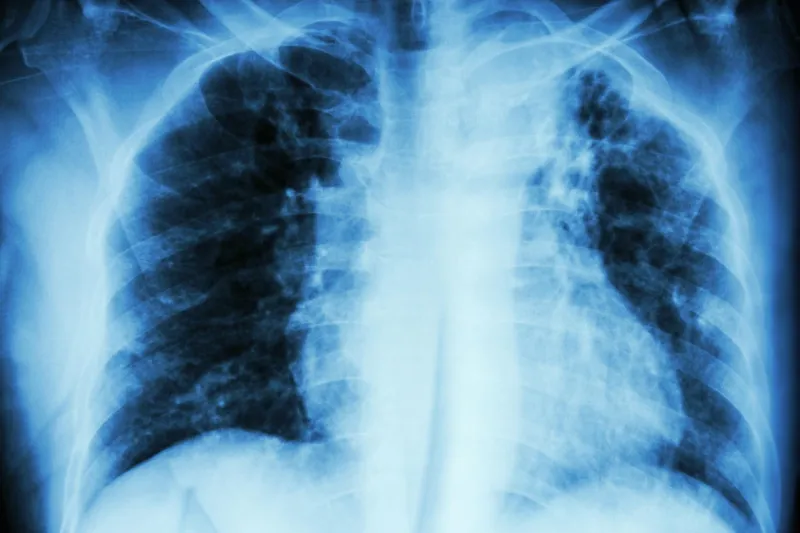

tuberculose pulmonaire infiltration interstitielle aux rayons x du poumon supérieur gauche due à une infection à mycobacterium tuberculosis

"Les toux virales sont très courantes à cette période en hiver et disparaissent généralement d'elles-mêmes", a déclaré le Dr Rachel. Cependant, si vous avez de la fièvre, un essoufflement, des douleurs dans la poitrine lorsque vous respirez, vous pouvez avoir une infection pulmonaire bactérienne ou une pneumonie".